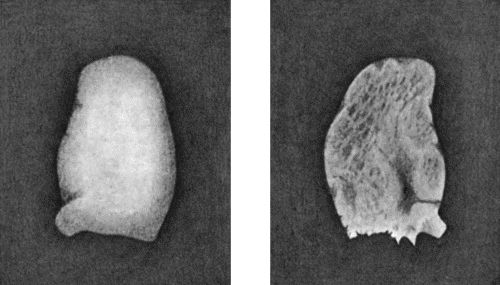

167.Loose Body from Knee-joint 541

168.Multiple partially ossified Chondromas of Synovial Membrane from Shoulder-joint 542